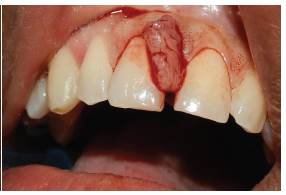

Se hace valoración clínica completa, se procede a realizar asepsia de la zona, aplicación de lidocaína al 2 % 1:80.000, mediante técnica anestésica infiltrativa se realiza incisión con hoja de bisturí número 15. Se levanta colgajo de espesor total para exponer la lesión; posteriormente aflora tejido nodular único, de consistencia firme y depresible, sangrante, doloroso a la palpación, de color rosa, de 4 mm de ancho por 9 mm de largo, de superficie lisa, base sésil. Se hace la extirpación completa de la lesión (figura 2A). Se realiza raspado y alisado radicular ultrasónico y manual. Se efectuó detoxificación de la raíz con fórmula magistral de ácido cítrico gel al 3 0% y hemostasia por dos minutos (figura 2B). Se sutura con Nylon 6-0 con puntos en ocho (figura 3A). Se realizó cita de control 8 días después de la cirugía para retirar suturas (figura 3B). Se cita nuevamente a los 15 días para realizar seguimiento. Se evidenció cicatrización de los tejidos blandos, y dos meses después se encontró un proceso de cicatrización dentro de lo esperado, sin complicación alguna.

La muestra extirpada se almacenó en formol tamponado al 10 % para su análisis histopatológico (figura 4A). Esta arrojó el siguiente resultado: los cortes mostraron mucosa oral con hiperplasia marcada del epitelio. A nivel de la lámina propia se observó infiltrado inflamatorio de predominio linfoplasmocitario de distribución heterogénea, proliferación fibrocolágena y de vasos de pequeño calibre (figura 4B) El diagnóstico definitivo es granuloma telangiectásico.